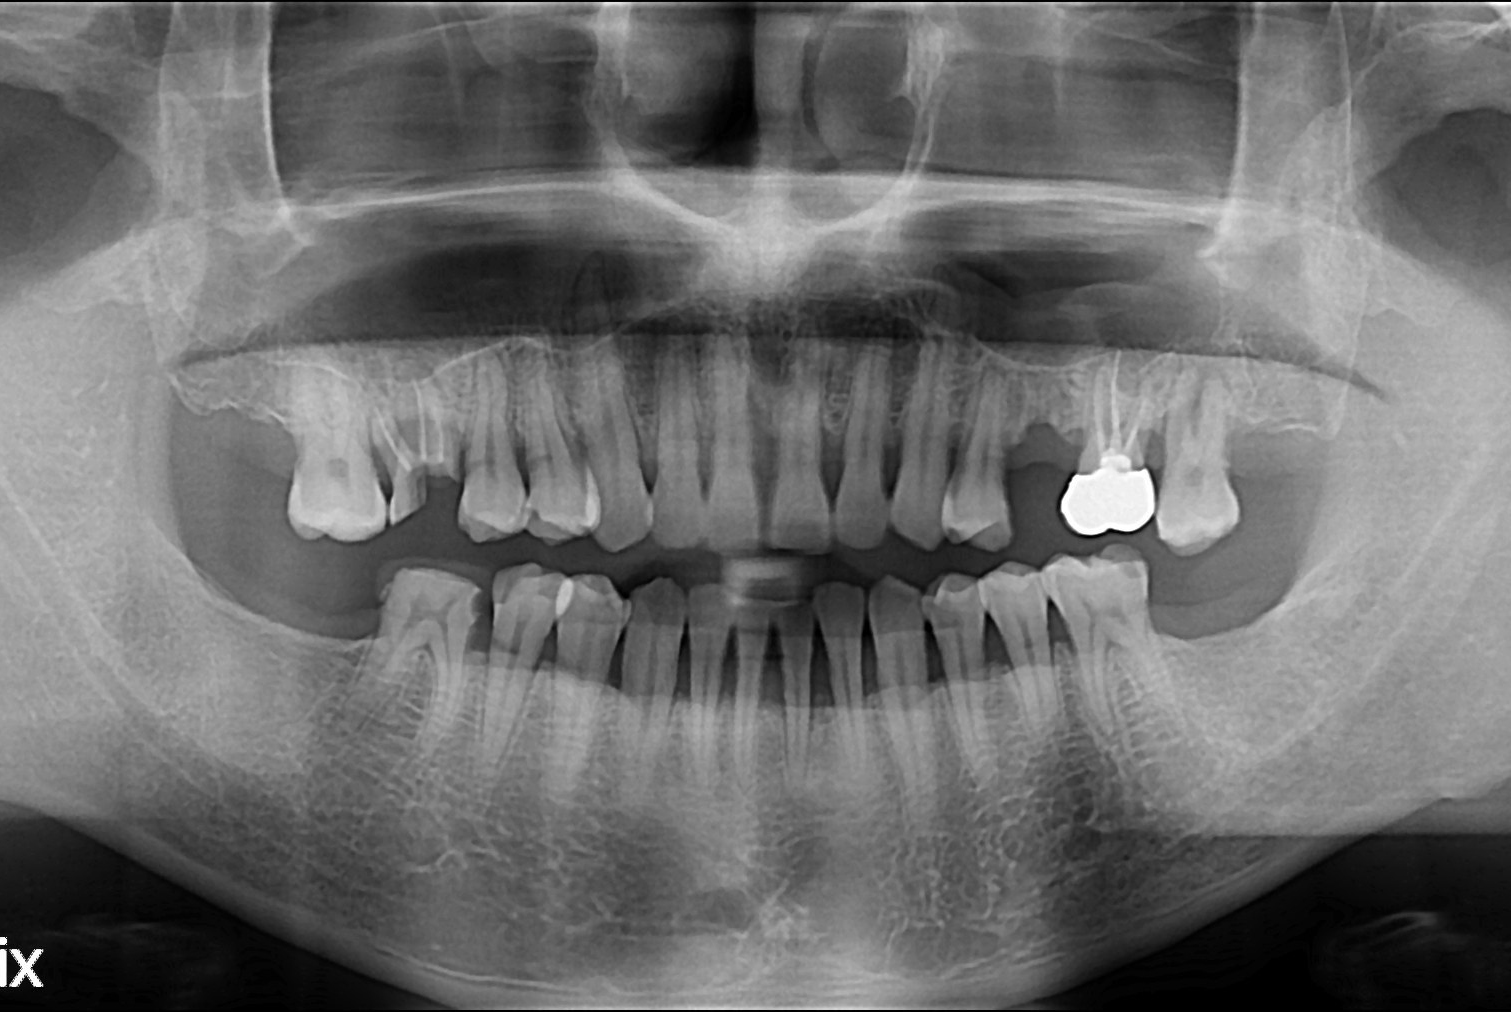

[임플란트] 임플란트

치료전 : 2019-07-18

세종치과는 많은 환자와 다양한 케이스를 바탕으로 항상 편안한 임플란트 수술을 제공하고자 노력하고,

오래동안 튼튼히 쓸 수 있는 임플란트 수술을 가장 큰 목표로 삼고 있습니다